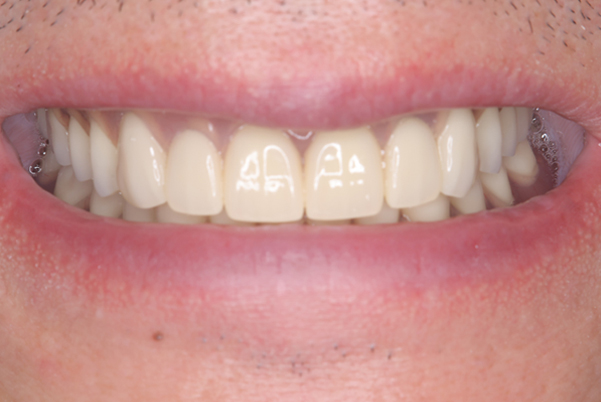

治療前後の口元の比較

こちらは、口を少し開いた時の治療前と治療後の

口元です。

正面から見た時にクラスプが目立たないように、

歯ぐきになじむ素材にて入れ歯を製作し、痛くなく自然に馴染み快適に生活を送れるようになりました。